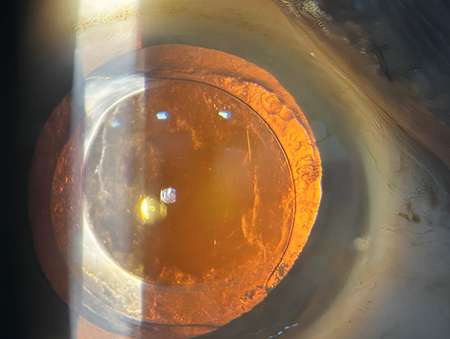

Chalazion – Successful Surgical Management At Vivaan ENT & Eye Clinic, we regularly manage eyelid conditions such as chalazion with safe, effective, and minimally invasive procedures. Recently, a patient underwent chalazion incision and curettage, performed by Dr. Veena Karkhele (Garje) under local anesthesia. The procedure was completed smoothly, and the patient had an excellent post-operative recovery with significant relief from swelling and discomfort.